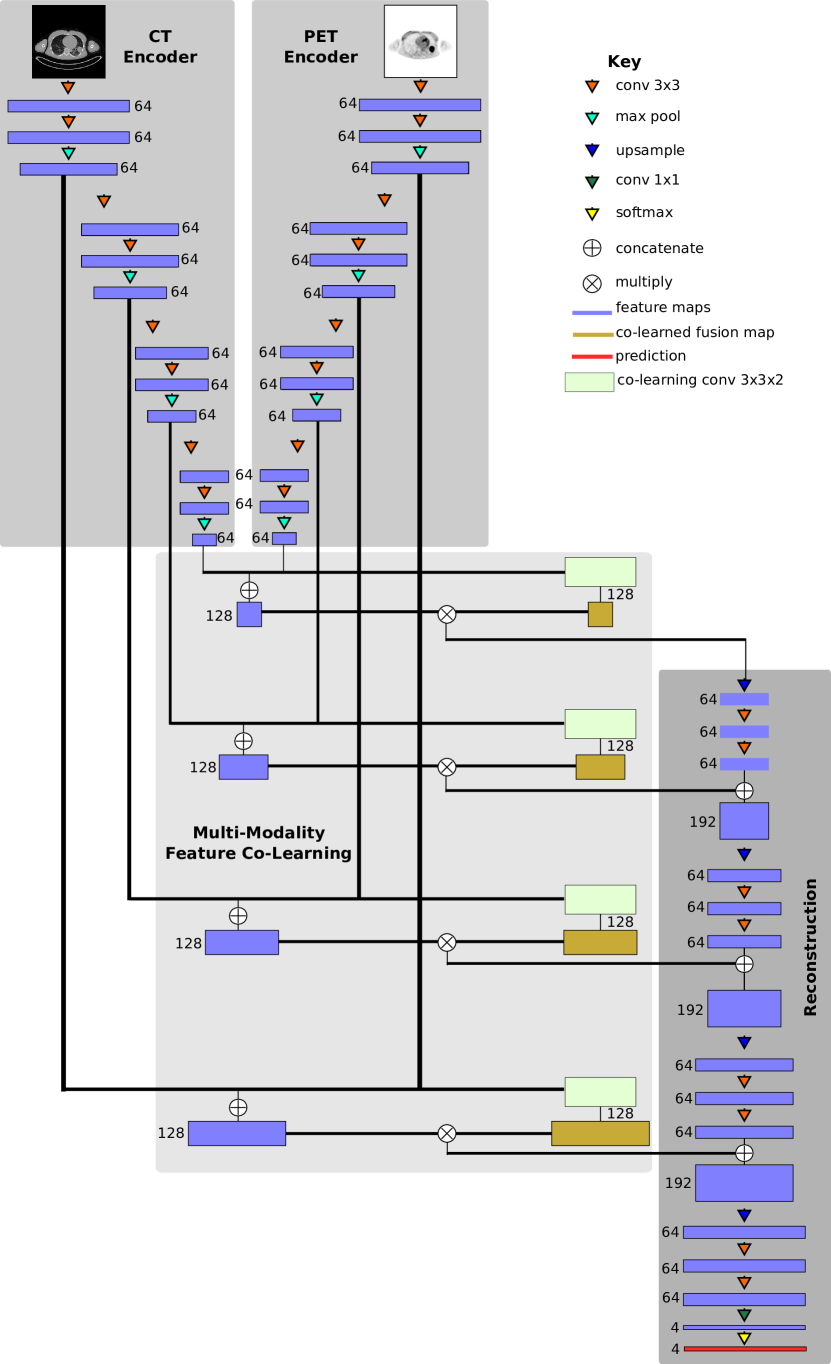

Fig. 1 shows the architecture of our proposed CNN; note that the number alongside each feature map in the figure refers to the number of output channels in the feature map. Our CNN comprises four main components: two encoders (one for each modality), one co-learning and fusion component, and a reconstruction component. The purpose of the two encoders is to derive the image features that are most relevant to each specific image modality; the input to each encoder is an axial 2D image slice. The co-learning component uses the modality-specific features produced by the encoders to derive a spatially varying fusion map to weight the modality-specific features at different locations. Finally, the reconstruction component integrates the modality-specific fused features across multiple scales to produce the final prediction map. The components are described in detail in the following subsections.

Our CNN contains an encoder for PET images and a separate encoder for CT images. The purpose of each encoder is to extract the visual features that are relevant to the input image modality. Thus, the encoders were designed with stacked convolutional layers in a similar manner to the deep CNNs that have achieved high accuracy in image classification tasks, e.g., AlexNet [40] and VGGNet [62, 63]. As shown in Fig. 1, each encoder comprises four blocks that each contain two convolutional layers for feature map generation and a max pooling layer to down-sample the feature maps.

II-D Multi-modality Feature Co-Learning and Fusion

The co-learning component consists of two parts: (i) a co-learning unit that is a CNN that learns to derive spatially varying fusion maps, and a (ii) fusion operation that uses the fusion maps to prioritize different features. Fig. 2 shows a conceptual example of the function of the multi-modality co-learning unit. The inputs to the co-learning unit are two feature maps and (each from a block of one modality-specific encoder), each of size with width, height, and channels. These feature maps are stacked to form , a tensor with number of modalities. The channels of are then convolved with the channels of a learnable 3D kernel of size , where is the width and height of the kernel, and is the number of modalities.

By performing a 3D convolution [67] without padding the modality dimension, we obtain for a given channel a feature map with a singleton third dimension where the value at location is determined from the neighborhood of both and :

| (2) |

We then squeeze the singleton third dimension to obtain an output feature map of size , the same width and height as the two modality-specific input feature maps and and double the number of channels, which is important for the weighting of modality-specific feature maps by the co-learned fusion maps as described below.

Our intention is that the co-learned fusion map controls the level of importance given to information from each modality at each location, in contrast to the global fusion ratio in PET-CT pixel intermixing [68, 69, 70]. Thus the co-learned fusion maps directly affect the input distribution of the learnable layers that immediately follow the co-learning unit. Hence, we do not normalize the output of the 3D convolution within the co-learning unit. As with the encoders (see Section II-C), we used a Leaky ReLU activation function to obtain the multi-modality co-learned fusion map:

| (3) |

where are the learned biases. Note that the multi-modality fusion map is obtained by the co-learning unit based on the spatial integration of the features from both modalities, since the 3D convolution operation considers the 3D neighborhood defined by the width, height, and modality of the stacked feature map .

The fusion operation (depicted in Fig. 3) integrates the modality-specific feature maps according to the values (coefficients) in the multi-modality fusion map, as follows:

| (4) |

where is the fused co-learned feature map, is the stacking operation, and is an element-wise multiplication. This process merges the two modality-specific feature maps and and weights them by the co-learned multi-modality fusion map , similar to pixel intermixing. Our CNN (Fig. 1) generates four fused feature maps, one for each pair of encoder blocks. These fused feature maps are passed to the reconstruction part of the CNN (see Section II-E).

II-E Reconstruction

The reconstruction part of our CNN creates a prediction map of the ROIs within the PET-CT image. It does this by integrating the co-learned feature maps from different encoder blocks and upsampling them to the dimensions of the original inputs. Similar to the encoders, the reconstruction component comprises four blocks each with one upsampling layer and two convolutional layers.

The input to a reconstruction block is the output co-learned feature map from a co-learning unit stacked with the output of any prior reconstruction block. The upsampling layer first doubles the width and height of the stacked feature map using nearest neighbor interpolation to enable eventual reconstruction of the detected regions at the same scale as the original input; this formulation is similar to that of a deconvolutional layer [71] but does not require any striding operations. The following two convolutional layers merge and refine the information from the stacked modality-specific feature maps. The concept behind each reconstruction block is to generate higher dimensional feature maps that better correspond to the features for different ROIs by merging lower dimensional information with features that were fused from multiple image modalities. As with the modality-specific encoders (see Section II-C), we use batch normalization [65] and Leaky ReLU [66] activations.

After the last reconstruction block, the output feature map has the same width and height as the input PET-CT image, with 64 channels in the third dimension. This is analogous to a final 64-dimensional feature vector for each pixel in the original image. We then use a 11 convolution to map these feature vectors into feature maps, where is the number of ROIs. This obtains for each pixel a vector corresponding to the observed activations for each ROI class as well as an ‘other’ class comprising all other image contents. We use the term ‘other’ rather than ‘background’ as this region encompasses the ‘true’ PET-CT background (areas of the image outside the field of view of the scanner that have a zero pixel value) as well as non-zero pixel areas within the image that are not of interest in the task (e.g., skin and subcutaneous fat of the chest wall, arms, etc.). Finally, we transform these observations into a probability or prediction map that corresponds to the likelihood of the pixel belonging to a particular class using the softmax function [72]:

| (5) |

where is the probability that the pixel with observation vector belongs to the region , is the -th element of vector and is the activation corresponding to region . The ‘other’ class (and hence the summation for regions in the denominator of Equation 5) is necessary to formulate the final output of our co-learning CNN as a set of probability maps. The ‘other’ class probability map ensures the sum of probabilities for each pixel has a total of 1 by capturing the probability that a pixel does not belong to any of the ROIs. The use of an additional class to compute the probability of non-ROI regions is a standard formulation that has been used in prior CNN research [73]. Fig. 4 is an example of the probability maps generated for the classes used in our experiments (lung fields, mediastinum, tumors), and the ‘other’ class.